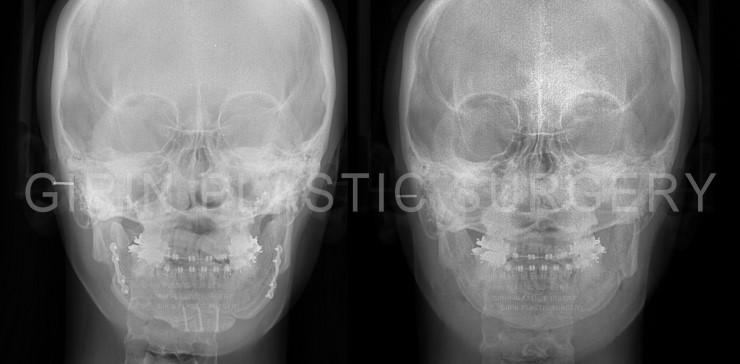

출처 아카이브 열기양악수술,윤곽수술 후 라인불균형, 이차각으로 인한 재수술케이스

20대후반 여성분으로 주걱턱 증상으로 2013년 양악수술, 윤곽수술을 받은 분의 재수술사례입니다.

육안으로도 이차각과 비대칭이 드러나 재수술은 이차각 및 라인교정과 아큐스컬프, 핀제거로 진행되었습니다.

엑스레이

양악, 턱끝수술 시 사용된 고정핀을 제거해드렸고, 상악에 위치한 핀은 일부 남겨두었습니다.